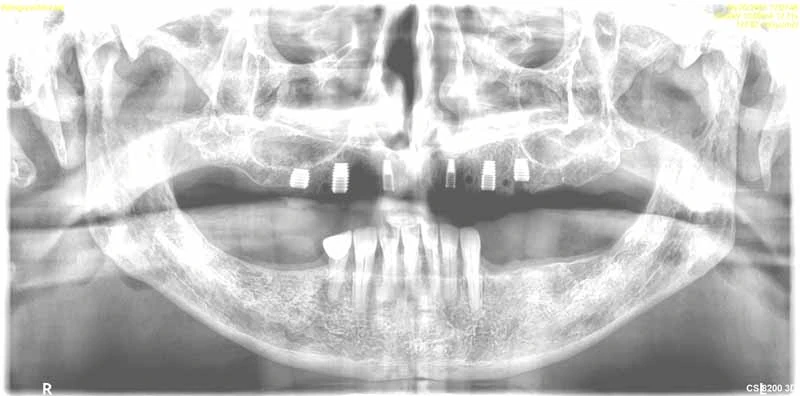

Dental Implant Gallery